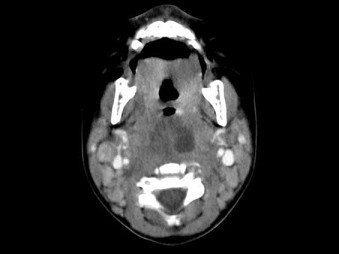

[多选题] 10个月大的婴儿,发热,曾患中耳炎,CT扫描如图所示,正确的描述或诊断是()A . 咽后壁软组织肿胀B . 其内密度不均C . 颈椎骨质未见明显异常D . 咽后壁脓肿E . 咽后壁寒性脓肿

[多选题] 10个月大的婴儿,发热,曾患中耳炎,CT扫描如图所示,正确的描述或诊断是()A .咽后壁软组织肿胀B .其内密度不均C .颈椎骨质未见明显异常D .咽后壁脓肿E .咽后壁寒性脓肿

[多选题] 10个月大的婴儿,发热,曾患中耳炎,CT扫描如图所示,请选择正确的描述或诊断()A . 咽后壁软组织肿胀B . 其内密度不均C . 颈椎骨质未见明显异常D . 考虑为咽后壁脓肿E . 考虑为咽后壁寒性脓肿

[多选题] 10个月大的婴儿,发热,曾患中耳炎,CT扫描如图所示,请选择正确的描述或诊断()A .咽后壁软组织肿胀B .其内密度不均C .颈椎骨质未见明显异常D .考虑为咽后壁脓肿E .考虑为咽后壁寒性脓肿